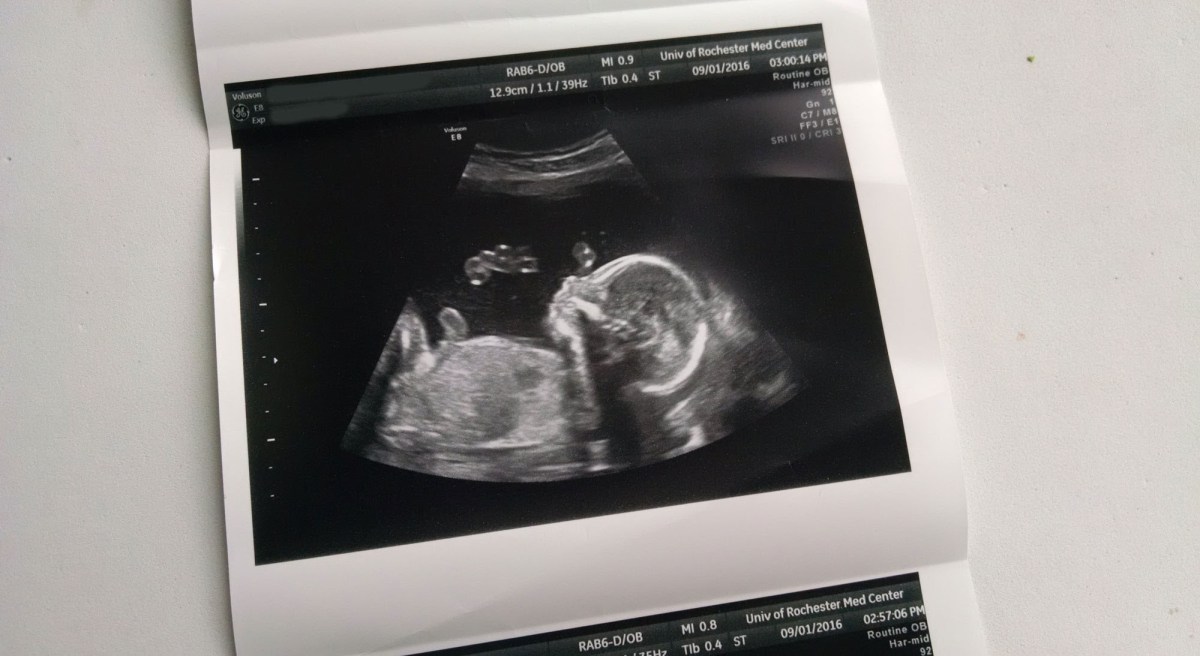

Then we had an appointment yesterday, and the new images told a better story. His physical problems are still there – but he is growing! He’s still small for his gestational age, but he added over 30 grams of weight per day over two weeks, which, in technical terms, means he’s crushing it! If his growth had stopped already we’d likely choose to induce soon, but now we’re almost certainly not going to do so before Christmas, and if he keeps growing we’re happy for him to stay inside for as long as he wants. Yesterday’s visit in many ways saved Christmas for us and our family.